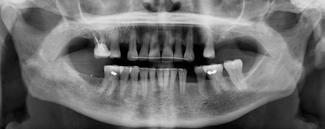

overbid (VOB). Papillen mellem 1+1 er betydeligt reduceret pga. fæstetab, og de mesialt kippede 1+1 har resulteret i en ”dark triangle”. Den facioorale funktion er for nuværende i.a. Panoramarøntgen (Fig. 1, I) viser marginalt knogletab i begge kæber og fravær af 8,7+7,8 og 8,7-8.